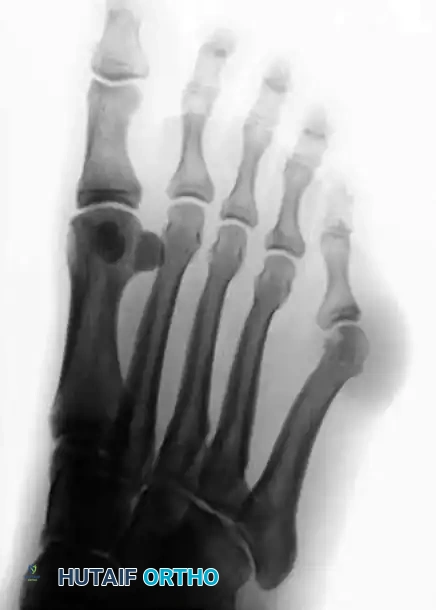

Radiographic Evaluation

Standard weight-bearing anteroposterior (AP), lateral, and oblique radiographs of the foot are mandatory for the accurate assessment of a bunionette deformity. The AP radiograph is utilized to measure several critical angles that dictate surgical decision-making.

Key Radiographic Parameters

- 4-5 Intermetatarsal Angle (IMA): Formed by the intersection of the longitudinal axes of the fourth and fifth metatarsals.

- Normal: Less than 8 degrees.

- Pathologic: Greater than 8 degrees indicates pathological divergence of the fifth ray.

- Fifth Metatarsophalangeal (MTP-5) Angle: Formed by the longitudinal axis of the fifth metatarsal and the longitudinal axis of the proximal phalanx of the fifth toe.

- Pathologic: Usually greater than 14 degrees in symptomatic patients.

FIGURE 83-40 Measurement of metatarsophalangeal-5 and 4-5 intermetatarsal angles for evaluation of bunionette deformity.

- Lateral Deviation Angle (LDA): This angle evaluates the intrinsic bowing of the fifth metatarsal shaft. It is formed by a line bisecting the metatarsal head and neck intersecting with a line drawn parallel to the medial cortex of the proximal fifth metatarsal shaft.

- Normal: Approximately 2.6 degrees.

- Pathologic: Averages 8 degrees in patients with a symptomatic bunionette.

FIGURE 83-42 Measurement of lateral deviation angle in the evaluation of bunionette deformity.

Type II: Lateral Bowing of the Metatarsal Shaft

Type II features an abnormal lateral bend or bowing of the distal third of the fifth metatarsal shaft. The 4-5 IMA is normal, but the Lateral Deviation Angle (LDA) is significantly increased.

FIGURE 83-41B Type II, lateral bowing of the fifth metatarsal.